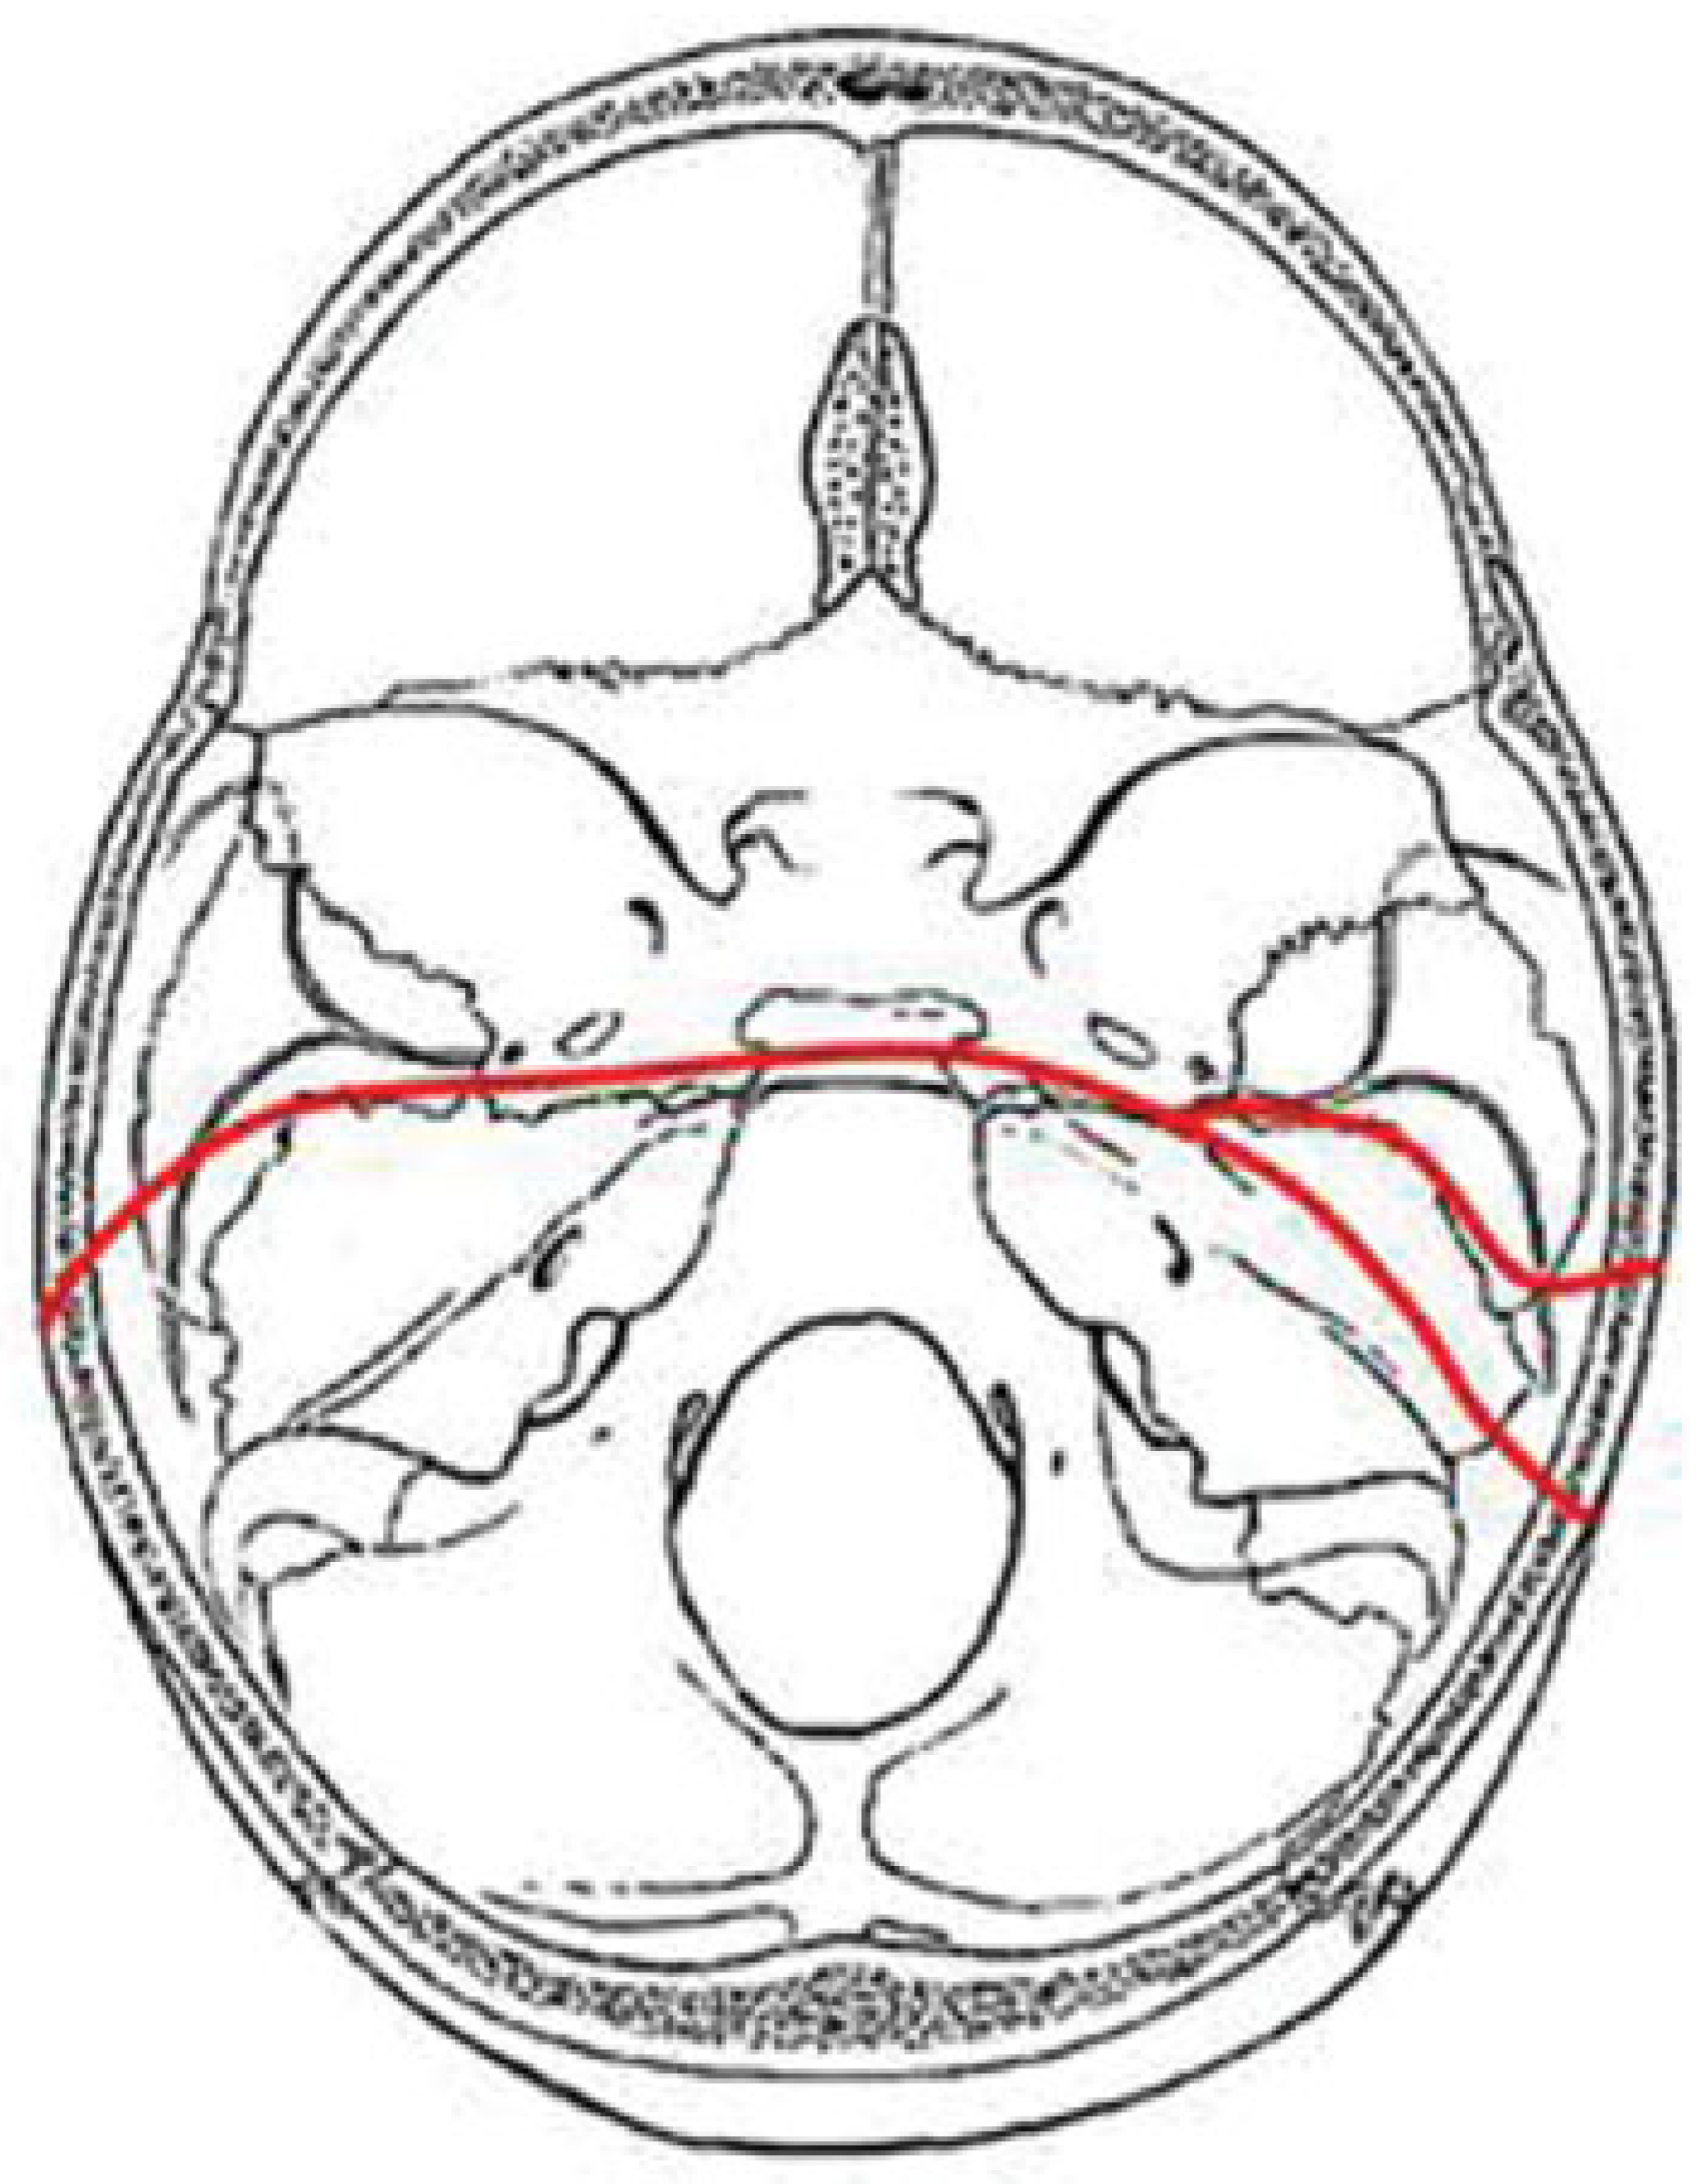

AT Pattern

The key to the identification of the AT pattern is the demon-stration of a coronal fracture through the sphenoidal plane at the base of the anterior clinoid processes. The exact position across the anterior sphenoid body varies slightly from the sphenoidal limbus to the roof of the extreme posterior ethmoid air cells. Most fractures pass through the roof of the sphenoid sinus anteriorly. The fracture typically begins in the squamous portion of the temporal bone, courses anteriorly to the sphenotemporal buttress, and then proceeds medially along the orbital surface (vertical plate) or the anterior cerebral surface (horizontal plate) of the sphenoid bone. The fracture intersects the sphenoid body at or slightly posterior to the junction, with the ethmoid bone producing the characteristic transverse fracture across the posterior aspect of the floor of the anterior cranial fossa. The fracture exits the sphenoid body through a similar pathway involving the contralateral greater wing along the orbital surface (horizontal plate) or the anterior cerebral surface (vertical plate). In severe fractures, the fracture will continue to propagate into the contralateral squamous portion of the temporal bone (Figure 5).

Figure 5. Composite drawing of the anterior transverse fracture pattern (left impact).